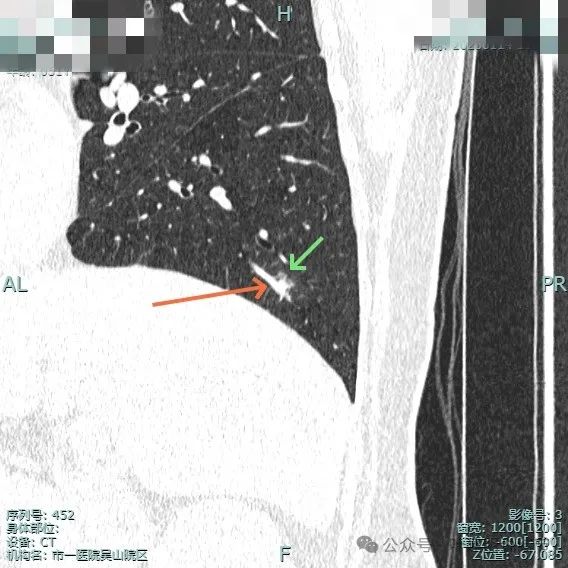

再看在我门诊时2025年1月14号复查的靶扫描影像:

靶重建显示边缘细毛刺、外围磨玻璃密度,中间实性成分明显,表面不平有浅分叶。

中间实性成分感觉边缘较清,缺乏收缩力,外围的磨玻璃成分整体轮廓较清,边缘有细毛刺征。

边缘细毛刺,不太锐利;外围磨玻璃成分,瘤肺界限欠清;中间实性成分明显但缺乏收缩力,实性部分没有明显毛刺征。

灶边有支气管扩张,表面不平,灶内实性成分无收缩力。